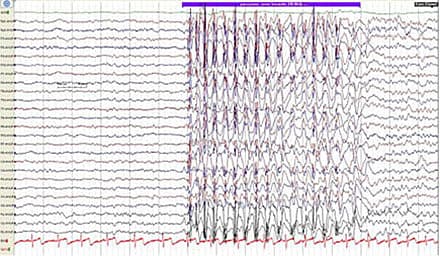

at dreje hovedet mod en stemme [4-6]. Efter anfaldet fortsætter de deres aktivitet og har ofte ikke selv bemærket noget. Under anfaldene er der bevidsthedspåvirkning, men det er uklart, præcist i hvilken grad bevidstheden er svækket. Der er typisk amnesi for anfaldene [7]. Absencer kan fremprovokeres af bl.a. søvnmangel, lys og hyperventilation [5]. Under absencer forekommer der generaliserede SW-EEG-forandringer med en frekvens på 3-4 Hz [8, 9]. Disse er karakteristiske og er en del af diagnosen BAE, men forekommer også ved absencer associeret med andre syndromer,

f.eks. juvenil absenceepilepsi og juvenil myoklon epilepsi [8]. Det interiktale EEG i BAE viser stort set altid forandringer i form af 3-4 Hz SW-paroksysmer, enten spontant eller provokeret særligt ved hyperventilation [9]. Differentialdiagnoser til BAE er bl.a. narkolepsi,

Taksigelser: Krisztina Benedek, Neurofysiologisk Afdeling, Rigshospitalet Glostrup takkes for lån af spike-wave-EKG og for video af patient.